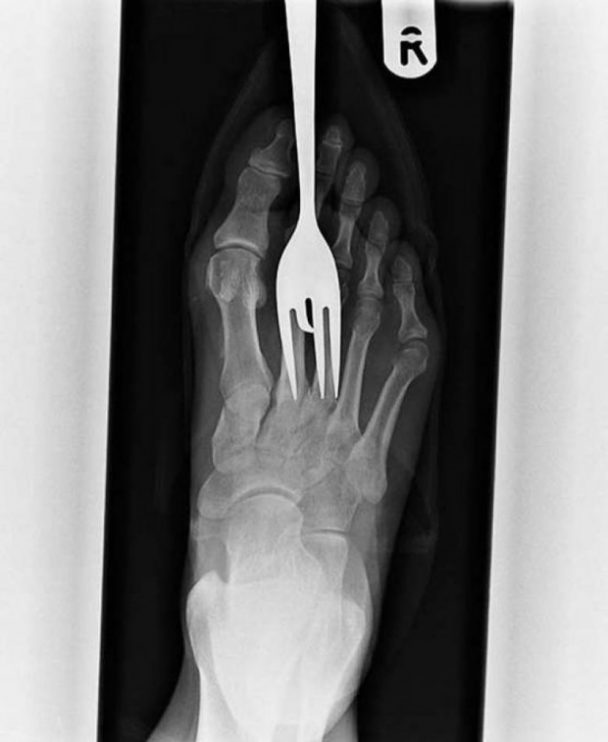

Röntgen filmlerinden "akıl almaz şeyler

Hastane koridorlarına düşenler bilir… Doktora görün, tahlilleri yaptır, röntgenleri çektir falan filan derken sayılmadan ömür gider. Gelin ki bu sefer ilginç şeyler çıkmış ki görün ağzımız açık kaldı…